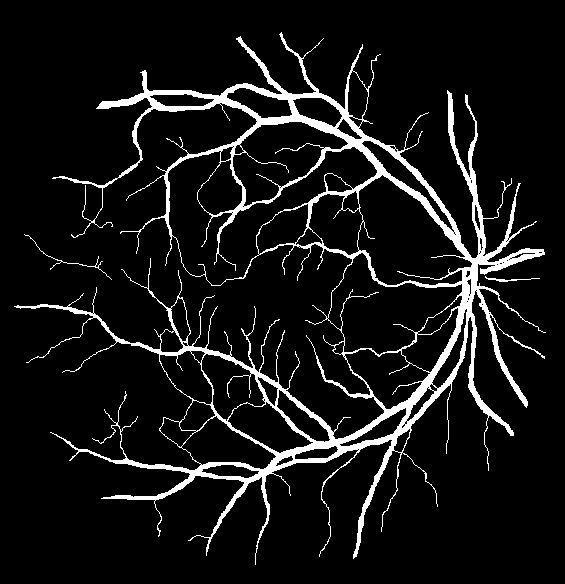

Refer to caption

(a) Original image

(b) Ground truth

(c) Level-I balancing

(d) Level-II balancing

(e) Original image

(f) Ground truth

(g) Level-I balancing

(h) Level-II balancing

Figure 6: Visual results after level-II balancing.

Impact of Level-II Balancing: This section analyzes the impact of applying Level-II balancing on top of Level-I balancing to the same sample images as in the previous sub-section. Specifically, the outcomes of applying Level-I and Level-II balancing are compared and graphically demonstrated in Figure 6. The application of Level-II balancing results in a significant performance boost over Level-I balancing, as indicated by higher values of all performance measures. Similarly, Figure 6 shows the visual outcomes of Level-II balancing for the sample DRIVE images along with their ground truths. The output segmentation masks show the detection of thin retinal blood vessels much closer to the ground truth binary mask than the images for Level-I balancing. The red rectangle is highlighted as a focus area for conveniently comparing the results. It can be concluded from comparing the results that Level-II balancing detects most of the vessel’s pixels, especially thin vessels, thereby significantly improving the sensitivity.